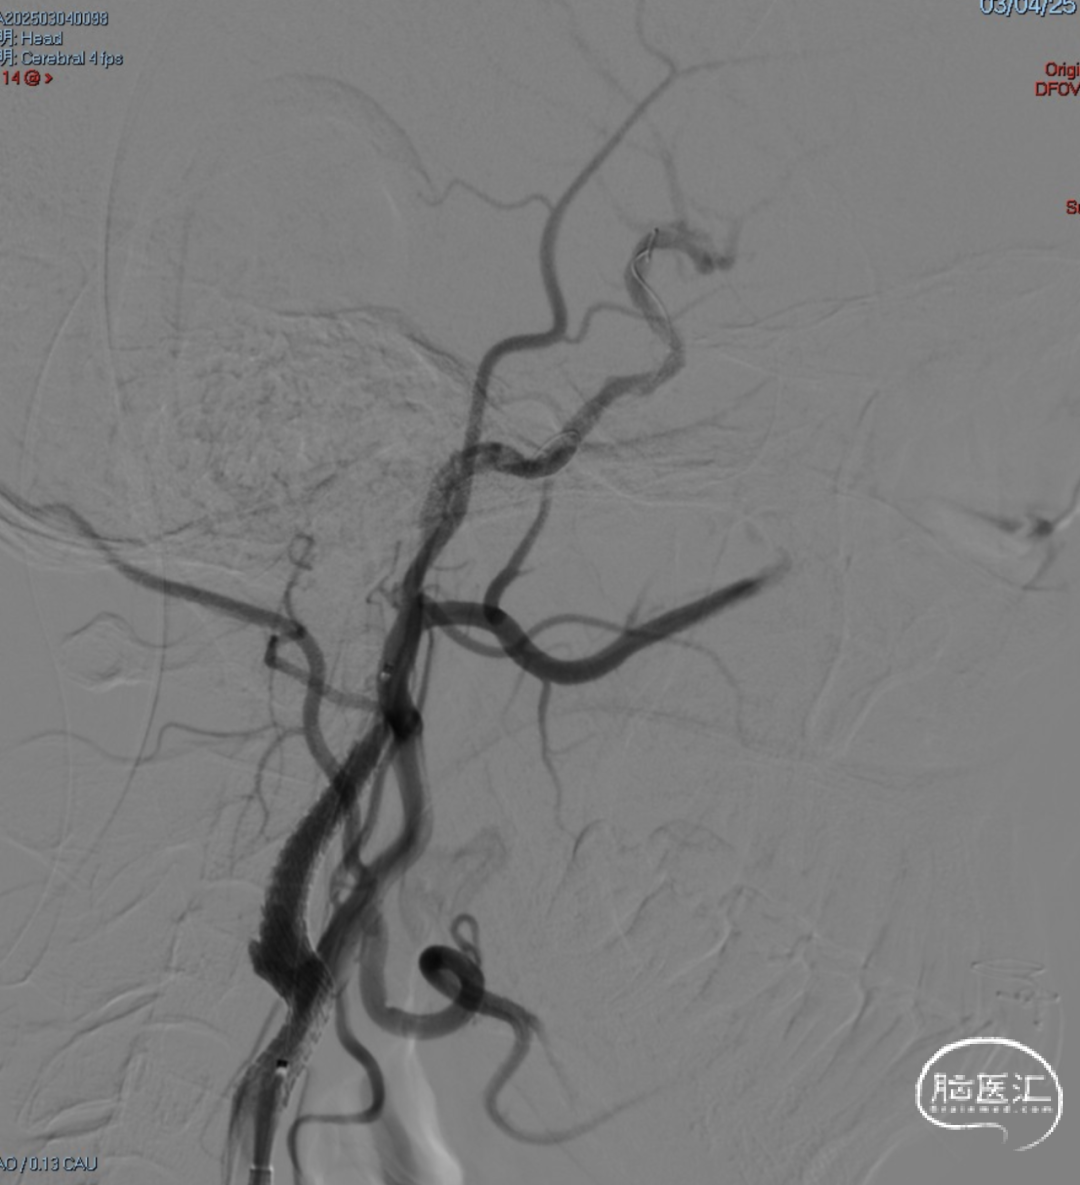

· 沿5F Tethys®中间导引导管送入3.5-5.5mm×300cm 保护伞于C5段释放,同轴送入Sterling 4.0mm×30mm 球囊扩张导管并覆盖C1段最狭窄处理,以14atm扩张维持约5秒并迅速释压,观察约1分钟患者心率及血压无明显变化,且意识及肢体功能无明显改变,复查造影示C1段狭窄较前明显改善。

· 撤出球囊导管送入7.0×40mm 自膨式支架,在路图及造影下定位,于狭窄处释放,再次造影提示C1段残余狭窄<10%,保护伞处近端造影剂充盈欠佳。

· 遂再次送入 3.0×12mm SacSpeed®球囊扩张导管于C1段远端以8atm扩张,并逐渐释放,同时跟进中间导管至C5段,继续前送中间导管在负压抽吸下将保护伞回收至中间导管内,并持续负压下将保护伞撤出,保护伞及抽吸注射器内无明显血栓碎片,撤出中间导管、8F Guiding。

术后即刻影像。

支架植入后造影提示残余狭窄约10%。术中患者生命体征稳定,术后患者恢复良好出院,继续抗血小板聚集及他汀类药物治疗。